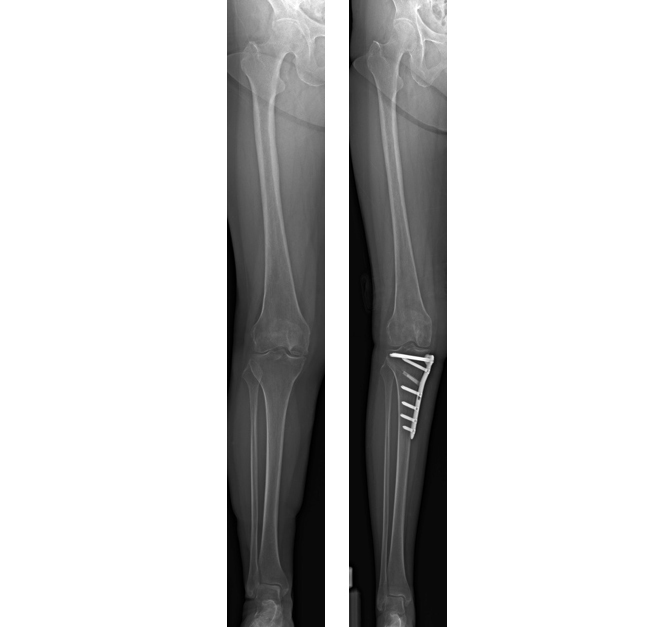

記事5『変形性膝関節症の膝周囲骨切り術(AKO)は術後のスポーツが可能に』で詳しくご紹介していますが、膝周囲骨切り術(AKO)にはいくつかの種類があります。今回適応した方法は、Open Wedge HTO(Open法)と呼ばれる方法です。

これは、脛骨の内側から外側に向かい骨を切り、内側を開いて専用のプレートや人工骨を入れ固定することで、矯正する方法を指します。

矯正する角度に応じて骨切部を開大し、人工骨を挿入して専用のプレートで固定します。人工骨は、時間が経過すると自分の骨に吸収置換され、いずれ自分の骨となります。